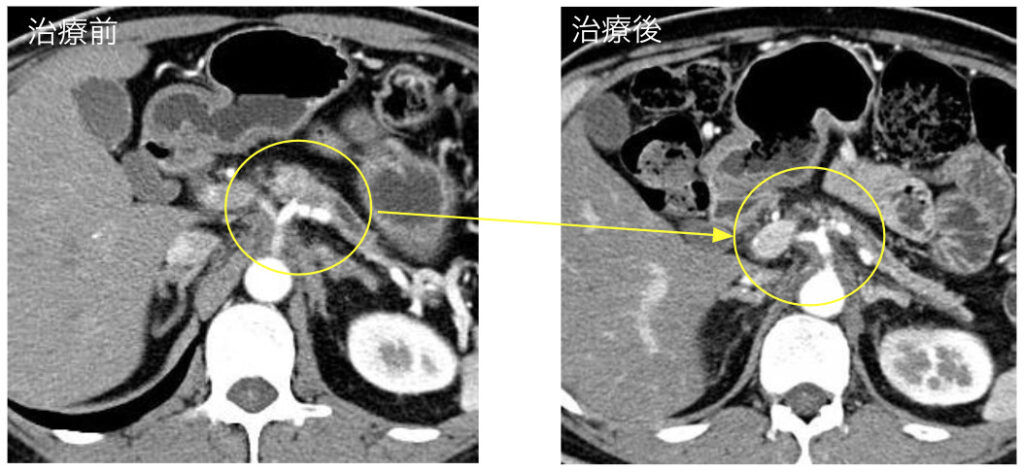

こぶし大に近い膵臓がんが縮小している